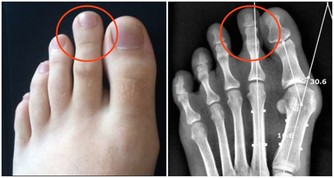

酒精在人體的代謝物——乙醛,攝入量過多,攝入時間過長,必會在人體囤積增加,繼而對許多組織和器官,特別是肝臟,造成極大傷害(進程如圖所示)!